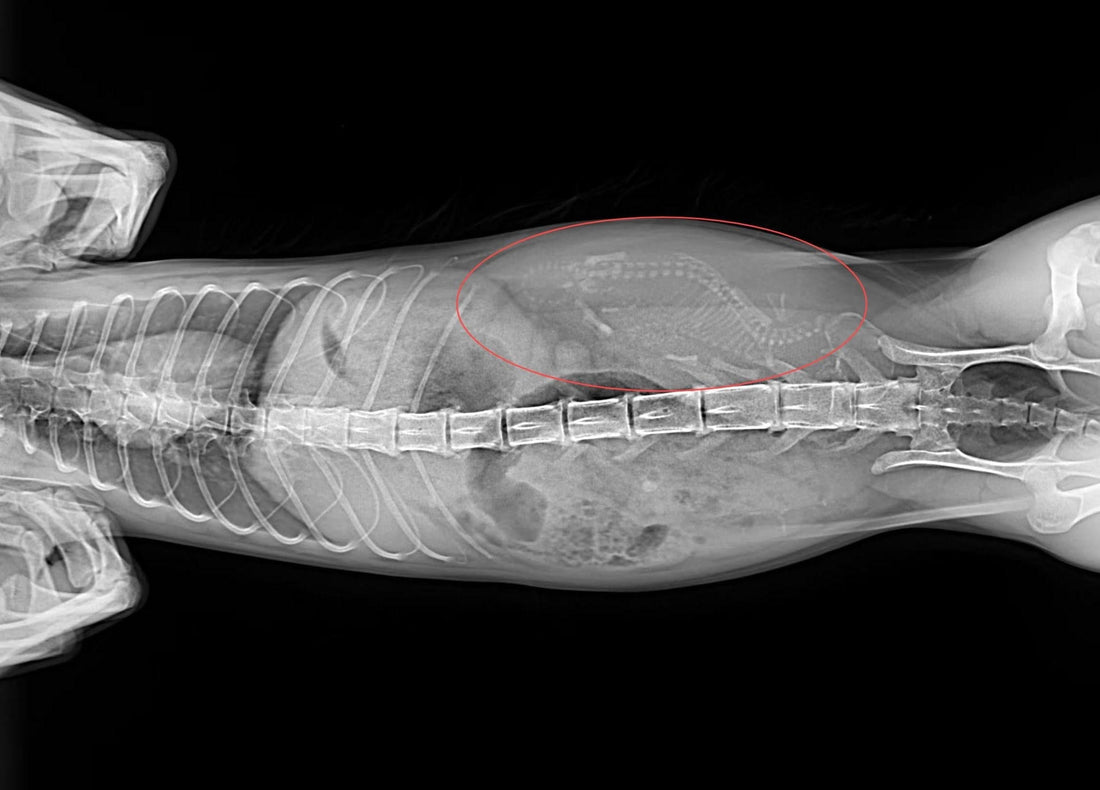

Here’s the ultrasound image when we first found out that Dante was expecting. It was a moment we’ll never forget—seeing those little signs of life inside her brought us so much hope.

As a way to honor Dante’s journey through motherhood and the little life she brought into the world, we wanted to share a special image. Below is a picture of Dante with her stillborn kitten. It’s a bittersweet memory, one that holds both love and loss. We hope this image helps convey the emotional bond we shared with our beloved pets during this journey.